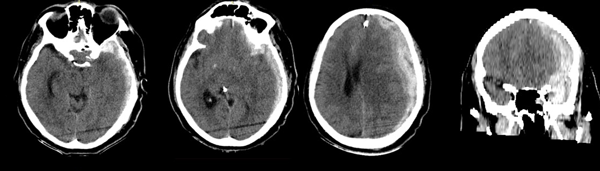

Ingresa por guardia por caída de propia altura, de la cual no se obtienen detalles por no haber estado acompañado en ese momento y no poder el paciente describir el evento con precisión. Se constatan signos menores de trauma (ligero cefalohematoma), lúcido y sin foco agregado. Seis horas después presenta rápido deterioro del sensorio, con Glasgow 12/15; se realiza TC que evidencia Hematoma Subdural Agudo mayor de 20 mm de espesor con desviación de línea media de 16mm y signos de herniación. El contenido heterogéneo del hematoma con signos de “jet” confirman la actividad del mismo. No se evidencian otras lesiones a nivel de parénquima (Figura 1). En su retorno a la sala de urgencias presentó evento convulsivo tónico-clónico asociado a anisocoria izquierda.

Figura 1. TC sin contraste al momento de su primer deterioro neurológico.